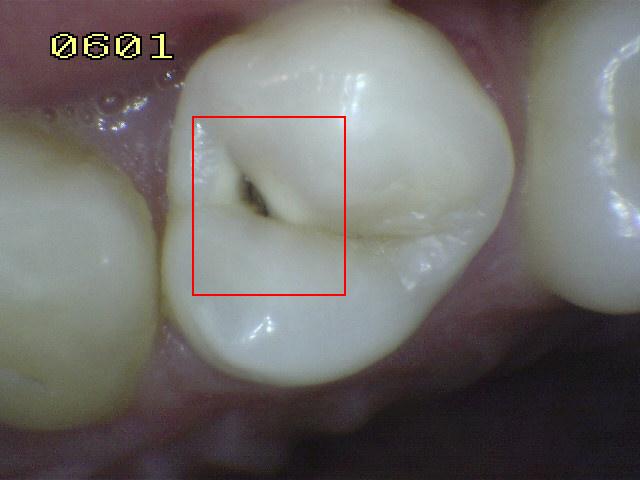

Código 6